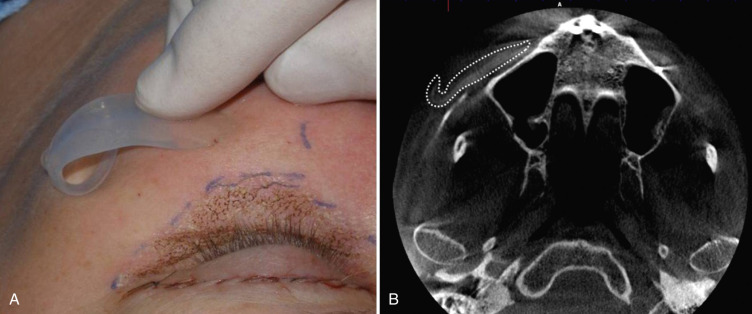

During preoperative evaluation, it is also important to evaluate the patient’s oral health. Placing implants in the presence of dental or periodontal disease can severely compromise the case and result in infection ( Fig. 7.6 ). Patients with oral disease must be treated to achieve a normal state of oral health prior to implant placement. All implant patients require a panoramic radiograph or computed tomography (CT) scan to rule out any osseous or dental or sinus pathology.

The procedure is begun by injecting about 5 mL of 2% lidocaine, 1 : 100,000 epinephrine transcutaneously in the subperiosteal plane along the region to be dissected. Since many surgeons outline the implant on the cheek, the marked area serves as a template for local injection, and the local is injected 1 cm past all margins. This usually includes the anterior maxilla, malar region, and anterior zygomatic arch region. Additionally, approximately 3 mL of the same anesthetic are infiltrated in the soft tissue planes in the mouth above the canine tooth, primarily to reduce incisional bleeding ( Fig. 7.8 ).